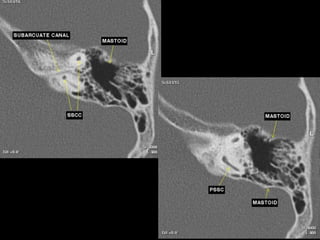

CT Temporal Bone Search Pattern with selected images :

Use both axial and coronal CT

images

Otic capsule:

•Superior semicircular canal (SCC)

•Posterior SCC (P)

•Lateral SCC (L)

•Vestibule (v)

•Aditus ad antrum (A)

•Cochlea

•Modiolus (mo)

•Basal turn (b)

•Middle turn (m)

•Apical turn

•IAC

•Facial n.

•labyrinthine segment (Fnl)

•geniculate segment

•tympanic segment

•Vestibular aqueduct